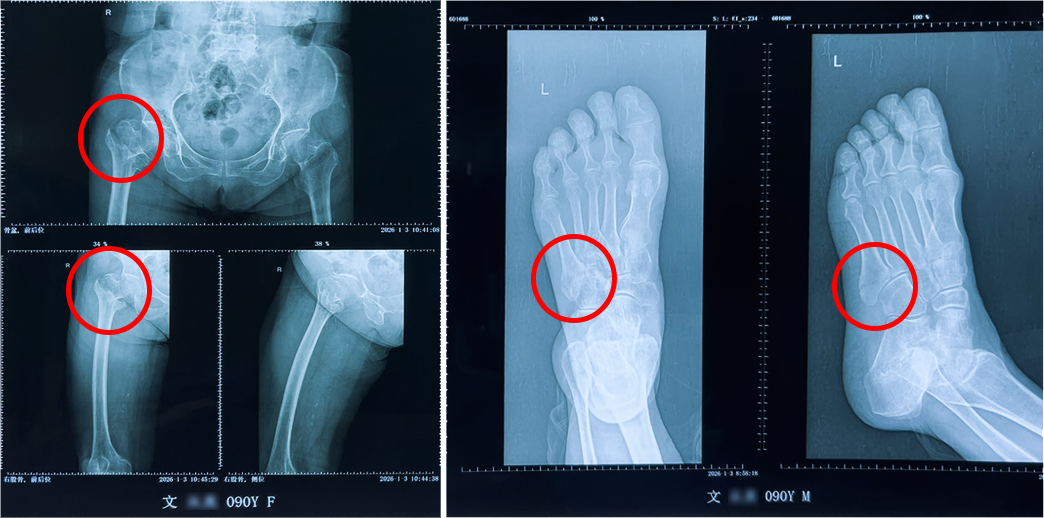

今年1月初,文奶奶在家中不慎摔倒,导致右股骨粗隆间骨折并伴有左足第五跖骨骨折,被紧急送入深圳永福医院。

双部位同期手术,精准拆解难题

1月5日,在充分准备和严密监护下,由骨科王林主任、尚艳强医生等组成的手术团队,为文奶奶成功实施了 “右侧人工股骨头置换术+左足第五跖骨骨折内固定术”。手术解决了髋部和足部的骨折问题,最大限度地减少了创伤和康复周期。